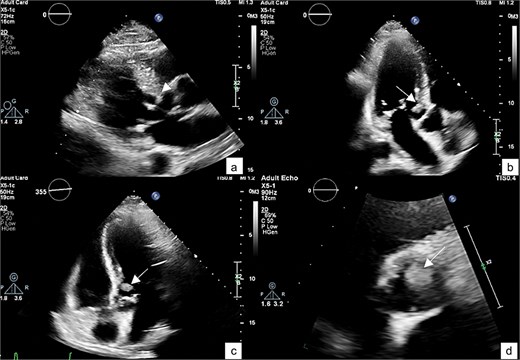

He was referred to our hospital for further evaluation by the cardiology and cardiothoracic surgery departments. On admission, he was afebrile with a heart rate of 62 beats per minute, blood pressure of 148/73 mmHg, and respiratory rate of 20 breaths per minute. No abnormalities were noted in any other system. Laboratory findings were unremarkable. An ECG demonstrated normal sinus rhythm. TTE re-evaluation revealed a normal LVEF of 72% with a 1.2 × 1 cm hypermobile cardiac mass attached to the basal anteroseptal wall near the LVOT without evidence of LVOT obstruction; there were no valvular lesions or thrombus seen (Figs 1 and 2). Coronary angiography showed normal coronary vessels. Due to its nature and clinical presentation, the patient was set for early surgical excision of the mass 3 days after admission.

A zoomed-in view of the mass with measurements of 1.2 × 1 × 0.9 cm (a–c) and in 3D echocardiography (d).